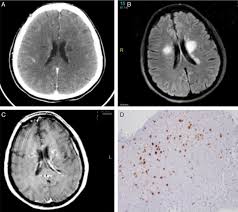

Este estudio examina el uso de nutracéuticos en neuropatías central asociada a Ehrlichia canis en un caso clínico canino. Se presenta una hembra de 1.5 años con signos neurológicos y sistémicos ligado a erliquiosis. El diagnóstico se confirmó mediante una prueba de antígeno rápido y estudios sanguíneos, por tanto, se inició un tratamiento que incluyó tetraciclinas y nutracéuticos. La evolución del paciente fue favorable con resolución de la mayoría de los síntomas en 30 días. Este caso destaca el potencial de los nutracéuticos como terapia complementaria en el manejo de complicaciones neurológicas de la erliquiosis canina. El objetivo del estudio es determinar la eficiencia del uso de Doxiciclina y Nutraceutico para tratar el sindrome neurologico multifocal producto de la infeción por erlichosis en un canino.